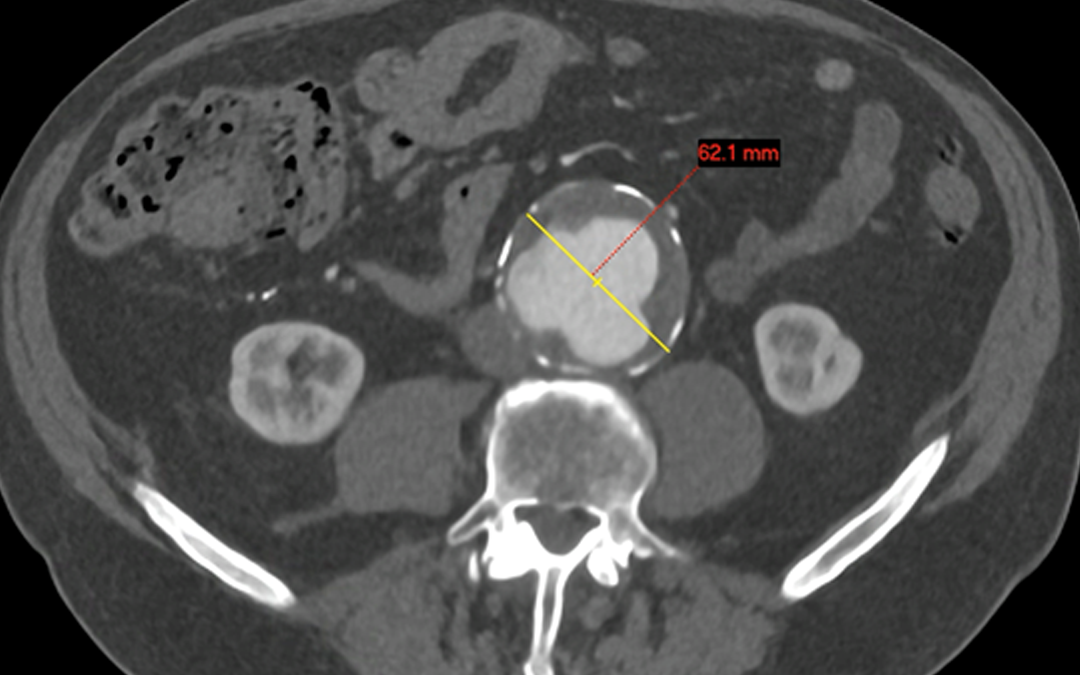

An aneurysm refers to an abnormally wide (dilated) blood vessel. This commonly affects the aorta, the main blood vessel in the tummy and chest. An Abdominal Aortic Aneurysm (AAA) affects around 3% of people over the age of 50. Why is an AAA important? A ruptured AAA...